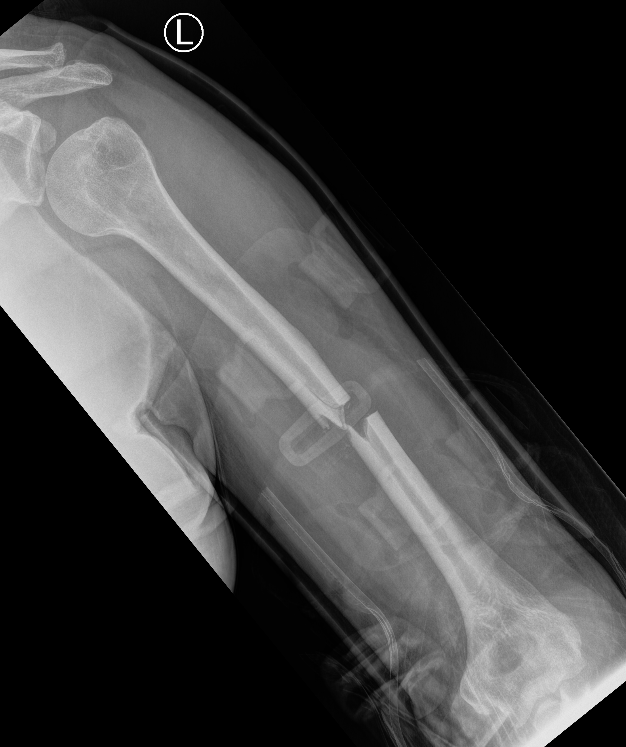

Prox humerus 1Prox humerus 2Prox humerus ORIFProximal humerus ORIF

Proximal third humerus ORIF of nonunion